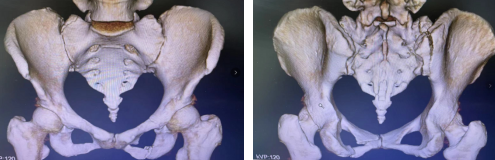

术前

患者骨盆多发骨折,即多处骨折,骨盆环非常不稳定,容易错位导致盆腔内的脏器受到挤压,必须尽快进行骨盆前环的固定。

2021年12月,36岁的李女士在下班回家路上不幸遭遇车祸,被120救护车送至betway在线登陆接受紧急救治。当时李女士被诊断为:骨盆多发骨折、闭合性腹部损伤、创伤性脾破裂、创伤性肝破裂、蛛网膜下腔出血、脑震荡、肋骨骨折(右侧第6、7)、右肺挫伤、右肾上腺挫伤、面部皮肤裂伤。李女士在我院综合外科治疗一段时间后,各项情况稳定,转入创伤骨科准备进行骨盆多发骨折的治疗。